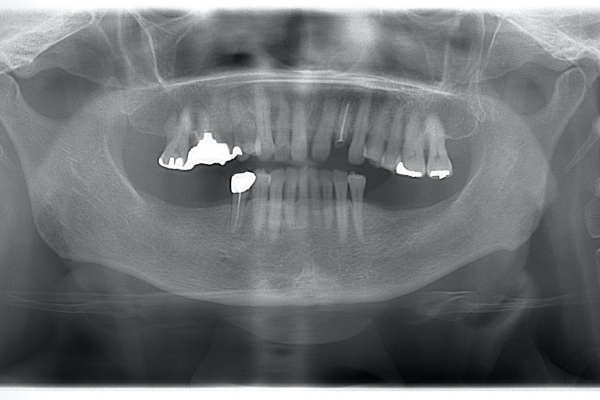

| 治療前で歯根が長いのがわかります。歯根がある程度長く無いと、MTMは行えません。 | MTM終了時のもの。フックが上の金属に接している。また根尖に透過像があるが、歯が動いた証拠です。 |

治療前で残存歯質がほとんどみられません。

残存歯質はないが、歯根は長いことを確認。

MTM治療開始時と終了後。右の根尖の透過像が実際に歯が動いた部分。